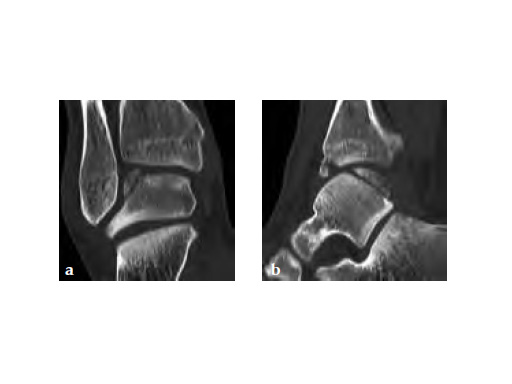

A 20-year-old construction worker fell from a 3 m height. He sustained a typical posterolateral impression and flake fracture of the talar dome.

Case provided by Christoph Sommer, Chur, Switzerland